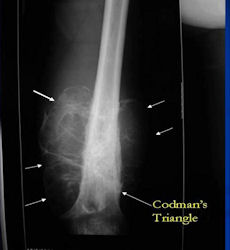

There are 3 radiographic presentations for osteosarcomas, depending upon the amount of osteoid/ossification and calcium deposition:

- Mixed sclerotic and lytic, permeative lesion most common radiographic presentation

- Purely osteoblastic, permeative lesion: dense sclerosis and osteoid production

- Purely lytic, permeative lesion: little osteoid production and/or minimal calcium deposition in osteoid

Conventional osteosarcomas are permeative lesions on plain radiographs (borders of the lesion cannot be clearly delineated)

- Wide zone of transition from lytic/sclerotic areas of tumor to normal bone

- Makes borders of lesion hard to define

- Most (90%) arise from the metaphysis of the bone

- Rarely (10%) arise from the diaphysis

- Most conventional osteosarcomas (90-95%) extend through the bone into the soft tissues and form a soft tissue mass outside of the bone

- Periosteal reactions such as the Codman’s triangle are apparent at periphery of soft tissue mass